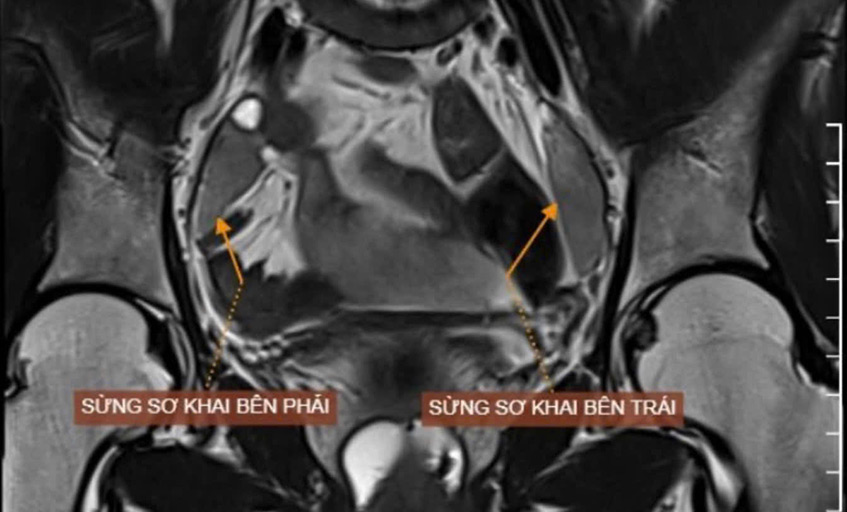

Đầu năm 2024, Hoài kết hôn. Biết vợ không có kinh nguyệt, người chồng động viên chị đến Bệnh viện Đa khoa Tâm Anh TP.HCM thăm khám. Kết quả chụp MRI xác định chị không có tử cung nằm giữa bàng quang và trực tràng, có một dải mô giống sừng tử cung nguyên thủy. Bác sĩ kết luận chị Hoài không có tử cung, một phần âm đạo bị bất sản (tức không phát triển).